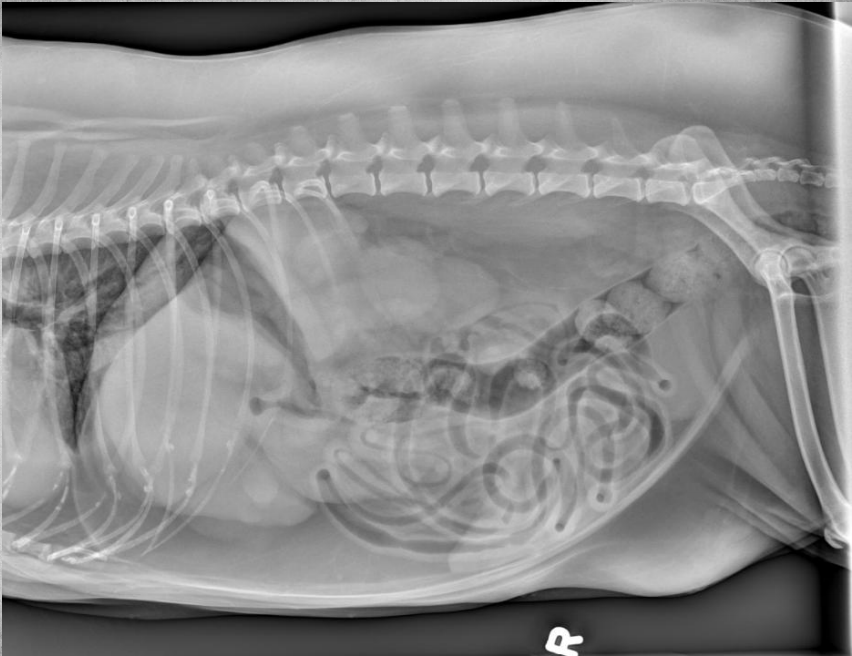

●10 yo female sterilized rottweiler

●Vomiting after every meal for 2 days

● Soft tissue opacity in the area of stomach

● Metal staple in colon

● Metal implant in one knee (from

previous surgery)

● Soft foreign body in stomach – grass,

fabric, wrapping paper

major organs in abdo cavity are hazy and poorly viewed, and lumen of stomach not viewable due to fabric foreign body in stomach.

cecum visible on VD, gas filled bubbles.